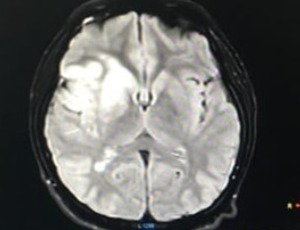

Study on Imaging Findings, Pathology and Treatment of Cerebellar Infarction

To explore the pathological mechanism and clinical treatment of cerebellar infarction through the clinical imaging changes of cerebellar infarction.